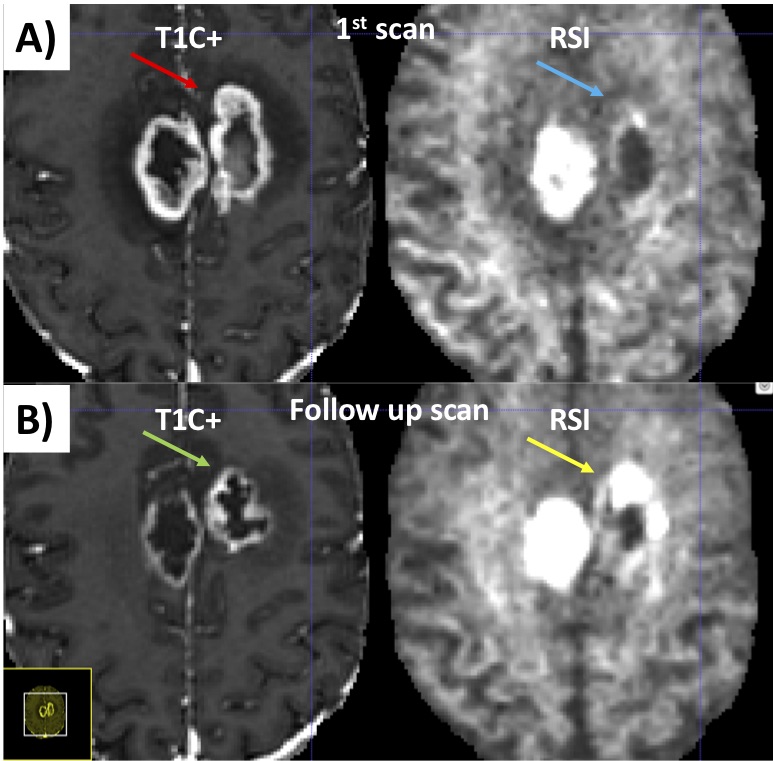

An example of segmentation for a cellular non-enhancing tumor case is shown in Fig 1. While the regions of FLAIR hyperintensity in the splenium of the corpus callosum and bilateral parieto-occipital white matter did not demonstrate significant enhancement, they showed increased RSI cellularity signal compatible with cellular infiltrative tumor (Fig 1A). These regions were segmented as tumor tissue in Fig 1B. An example of segmentation for a case with only post-treatment changes is shown in Fig. 2. The red arrow in Fig 2A demonstrated peripheral nodular enhancement at the anterior margin of the surgical cavity but the RSI cellularity map (blue arrow) did not demonstrate RSI cellularity signal in the enhancing regions or surrounding edematous tissue, suggesting post-treatment changes rather than recurrent tumor. This was confirmed on the follow-up scan (Fig 2B) where this region of nodular enhancement improved (green arrow) and tissue necrosis increased (yellow arrow) as shown by the very high RSI signal. Tumor segmentations with several variations of the Deep Learning model with different inputs are shown in Fig 3 for an individual test subject and the average Dice scores over the entire testing set is shown in Table 1. Adding RSI cellularity to the combination of T1 pre, T1C+ and FLAIR sequences increased the Dice score from 0.50 to 0.65. Although adding ADC to T1, T1C+, and FLAIR sequences also increased the Dice score, the increase was less pronounced than with RSI (0.60 ± 0.31 vs. 0.65 ± 0.24)." Fig 4 demonstrates an inverse relationship between volume of enhancing cellular tumor (both T1C+ and RSI positive) and the overall survival for patients with RSI scans within 180 days following surgical resection (n=20).

Fig. 2. Example case of a pure post-treatment changes. A) Initial post-surgical study. The red arrow demonstrates peripheral nodular enhancement at the anterior margin of the surgical cavity but the same region on the RSI map (blue arrow) does not demonstrate high cellularity, suggesting post-treatment changes rather than recurrent tumor. B) On the follow-up study, this region of nodular enhancement has resolved (green arrow) and tissue necrosis is now present (yellow arrow) as shown by the very high RSI signal.